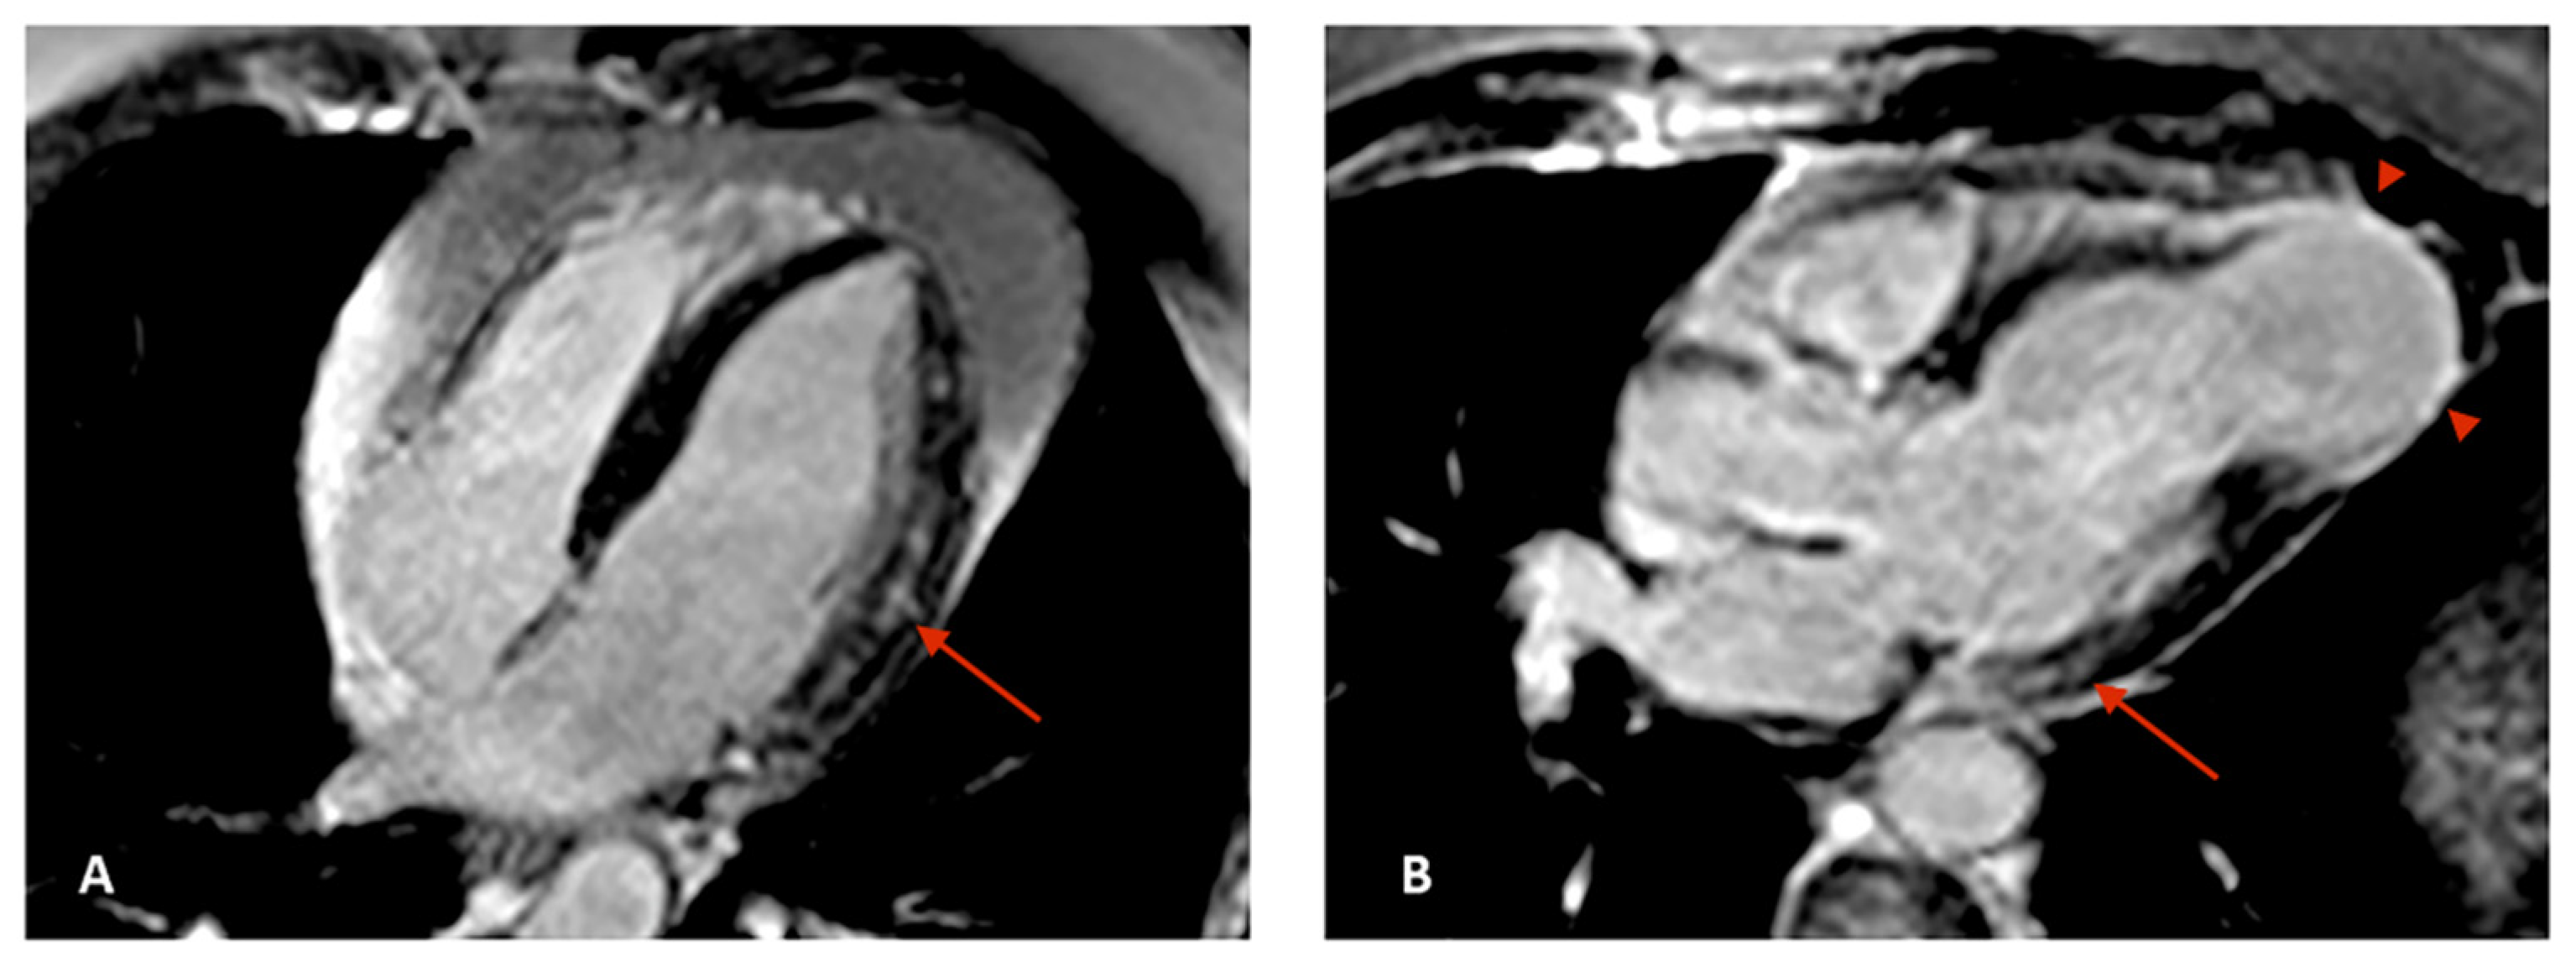

5. Cardiovascular Magnetic Resonance